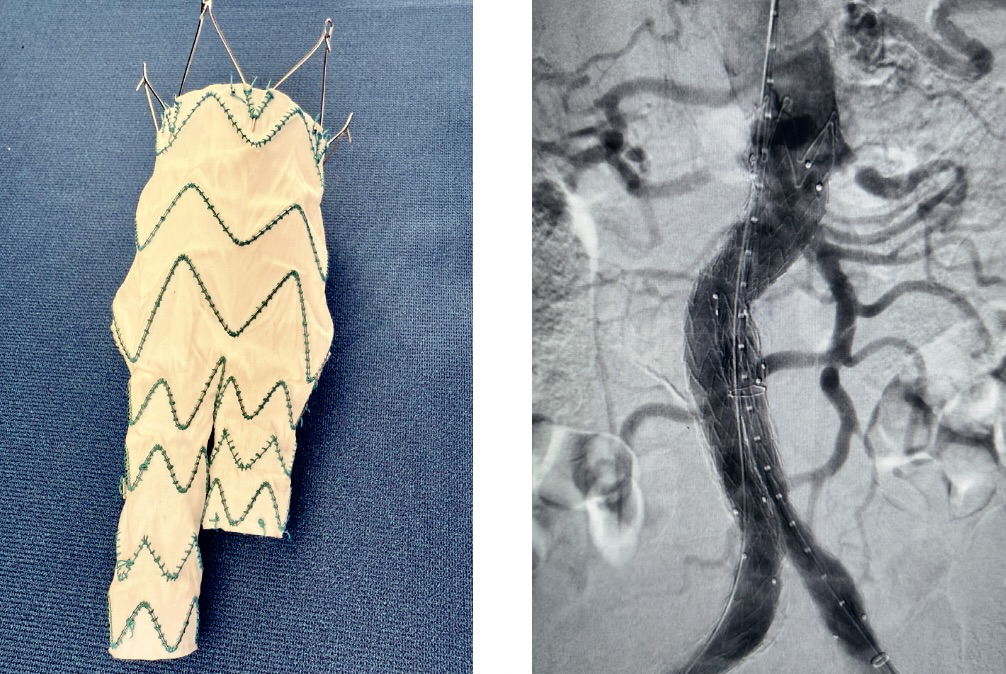

Безусловно, очень важны как мануальные навыки врача, так и его интеллектуальные способности: правильные показания к операции и диагноз на предоперационной подготовке, анализ обстановки и быстрое принятие правильных решений во время операции, умение использовать современные материалы. В сосудистой хирургии появляются все новые и новые материалы: стенты, стент-графты, так называемые эндопротезы, или, к примеру, стенты, содержащие активные компоненты, помогающие разрушать атеросклеротическую бляшку в сосудах и предотвращающие её дальнейшее развитие. Эти современные технологии помогают сосудистой хирургии постоянно развиваться.

Что касается лечения, у сосудистых хирургов есть большой арсенал инструментов, позволяющих лечить как на основе стент-графтов, так и с применением рентген-технологий в рентген-операционных, причем при лечении как срочных, так и хронических состояний - аневризмах грудного отдела аорты или брюшного отдела и смешанных аневризм всех отделов аорты.